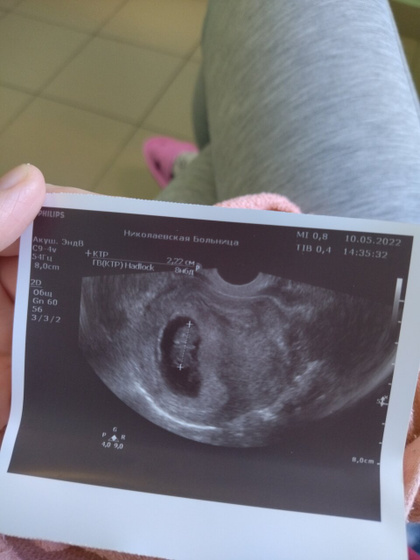

Лежу в стационаре уже неделю. Сегодня сделали УЗИ — отслойка в стадии организации, жидкости нет, небольшой тонус матки. Моё зёрнышко за эту неделю выросло на одну неделю и один день ??? по размерам меньше чем срок по МЦ, но это вроде не страшно) надеюсь на скорейшую выписку, старший сынок очень скучает и я тоже(